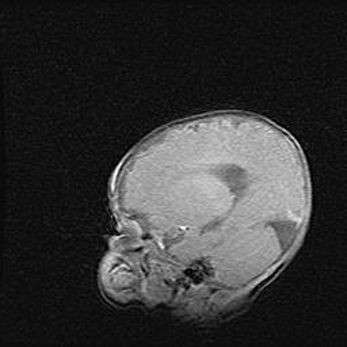

Аномалия Денди-Уокера. Признаки гипоплазии мозолистого тела.

Возраст: 5 месяцев 3 дня

Вес: 5550 г

Пол: мужской

Окружность головы: 39 см

Срок гестации: 40 недель

Аномалия Денди-Уокера – это порок развития головного мозга, для которого характерна триада симптомов: гипотрофия или аплазия червя мозжечка и/или полушарий мозжечка, расширение четвёртого желудочка с формированием ликворной кисты задней черепной ямки, гипертензионная гидроцефалия различной степени.

Гипоплазия мозолистого тела относится к дефектам внутриутробного этапа развития мозговой ткани, возникающим в процессе закладки структур головного мозга, что происходит на начальных этапах развития эмбриона.